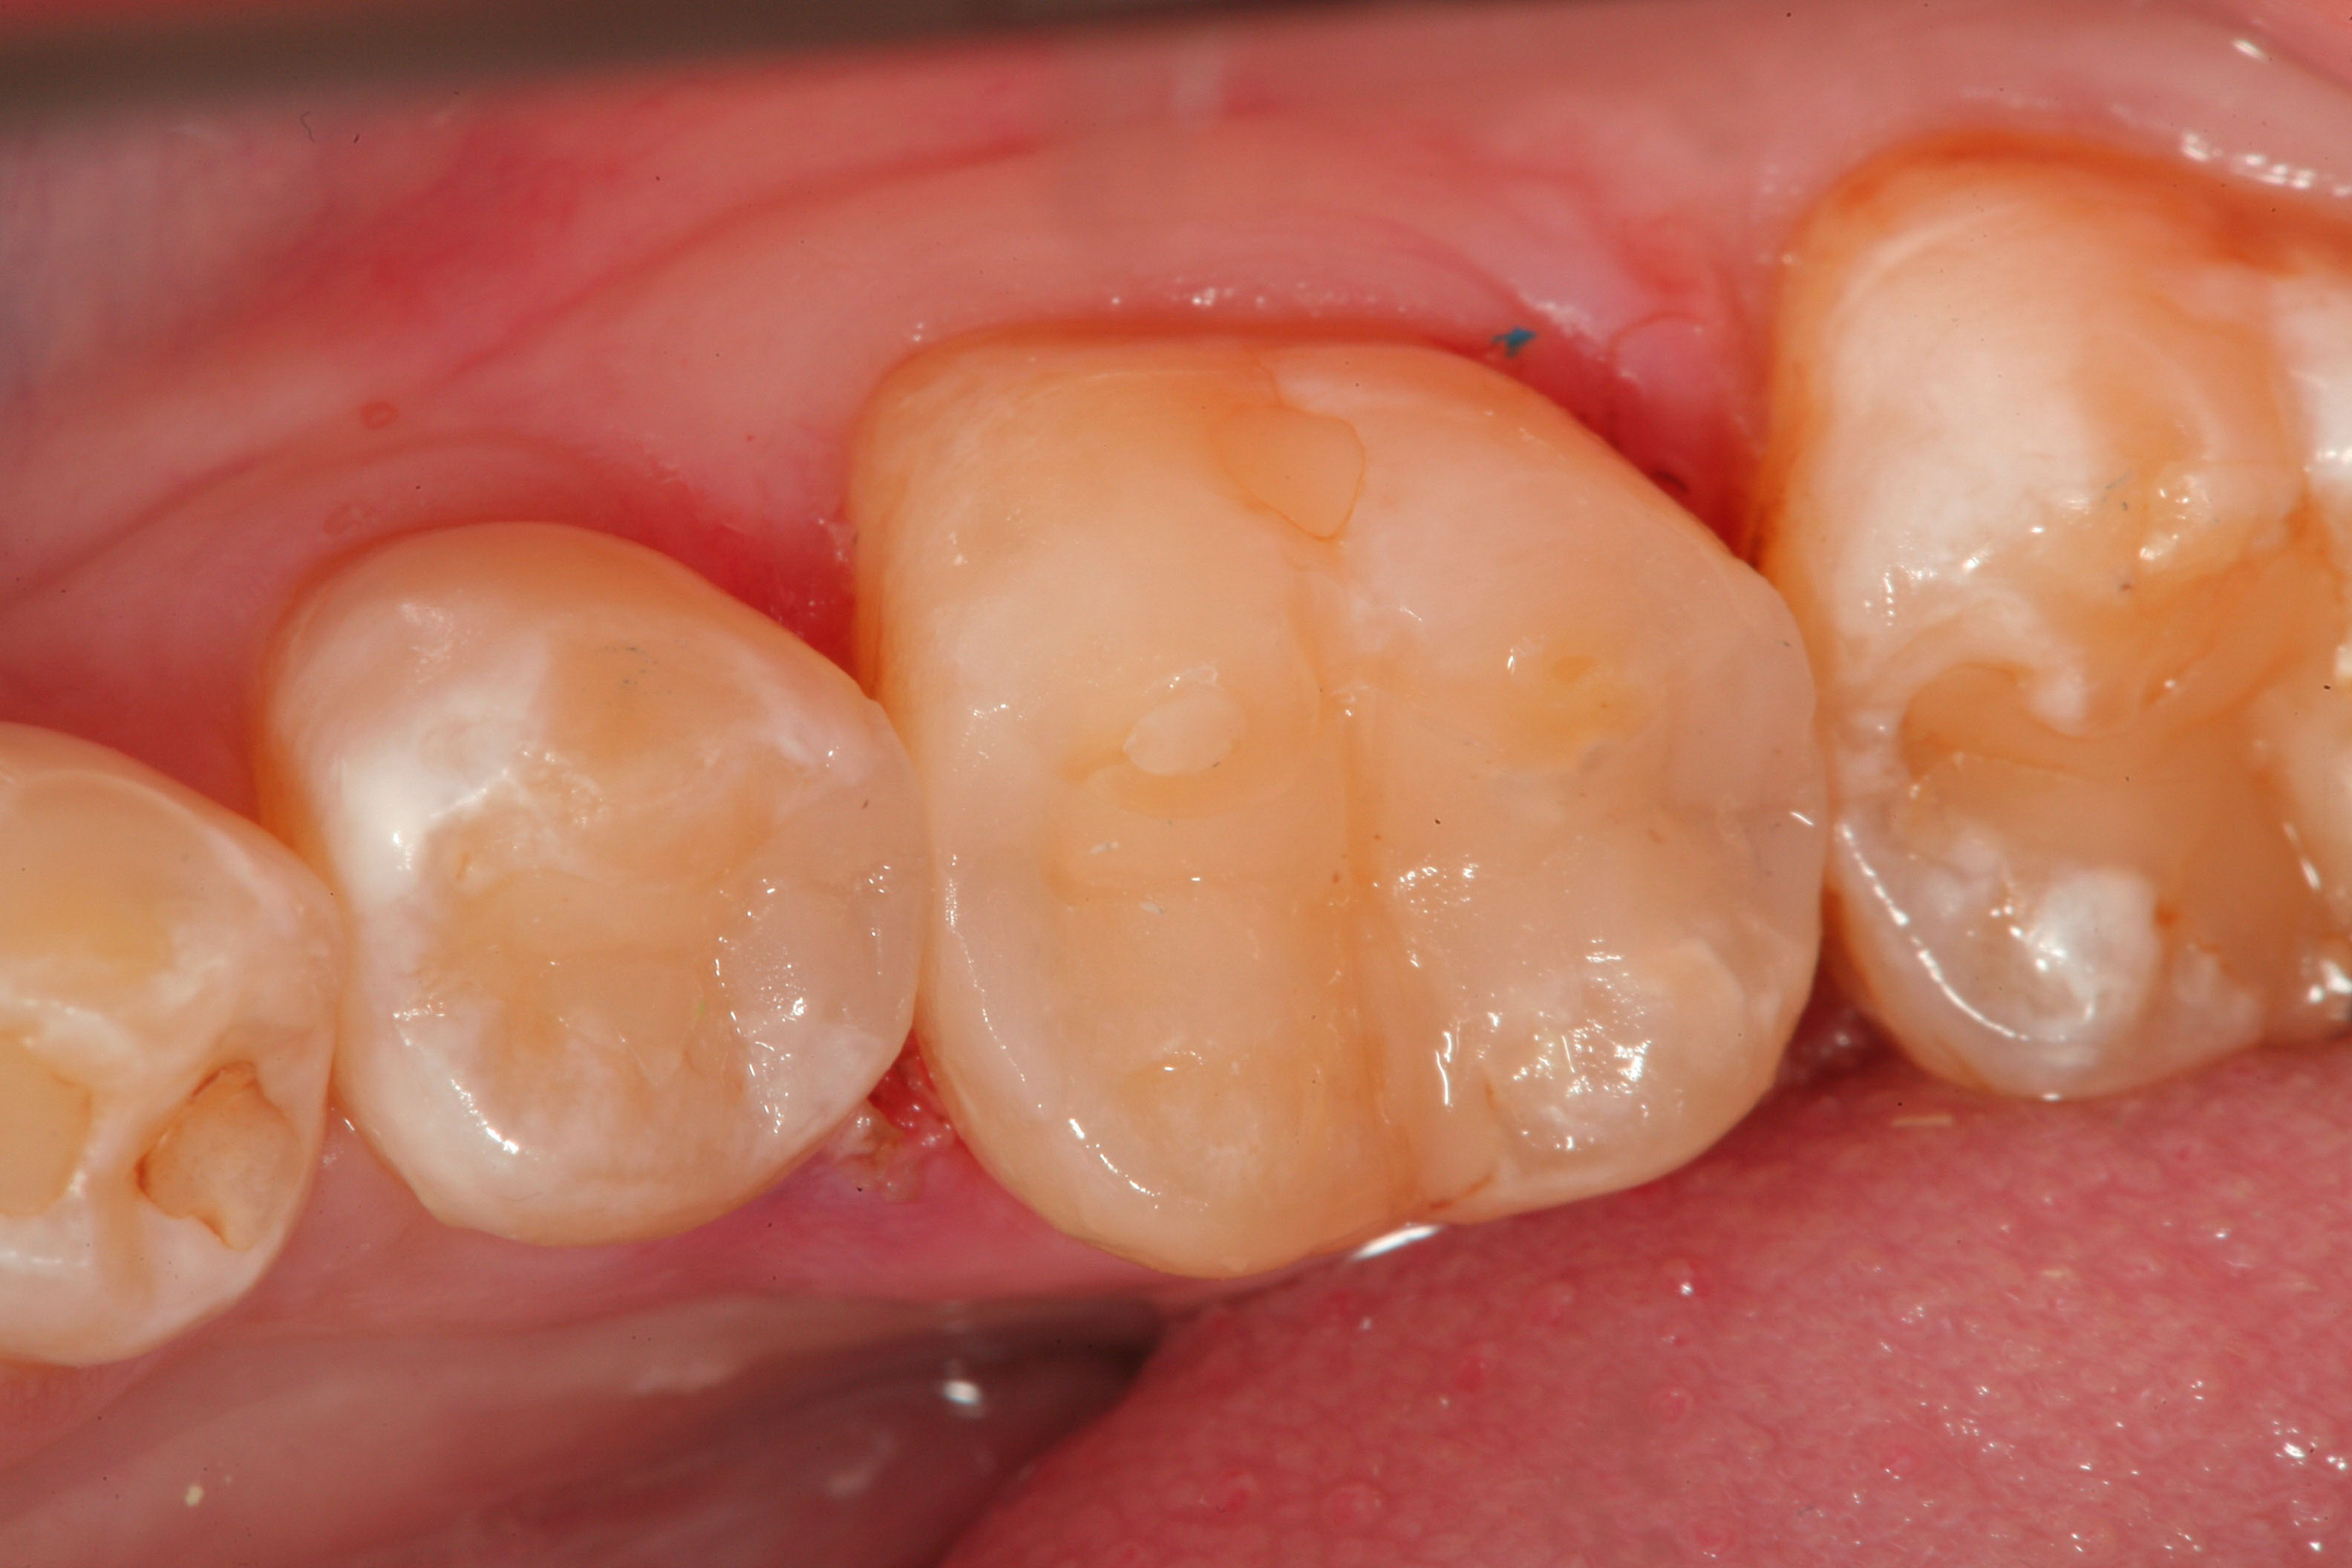

Fig 7. After slot preparation in the distal marginal ridge of tooth No. 5, proximal decalcification and decay at the dentino-enamel junction is clearly seen, although this lesion was not fully visible on radiographic examination.

Figure 7